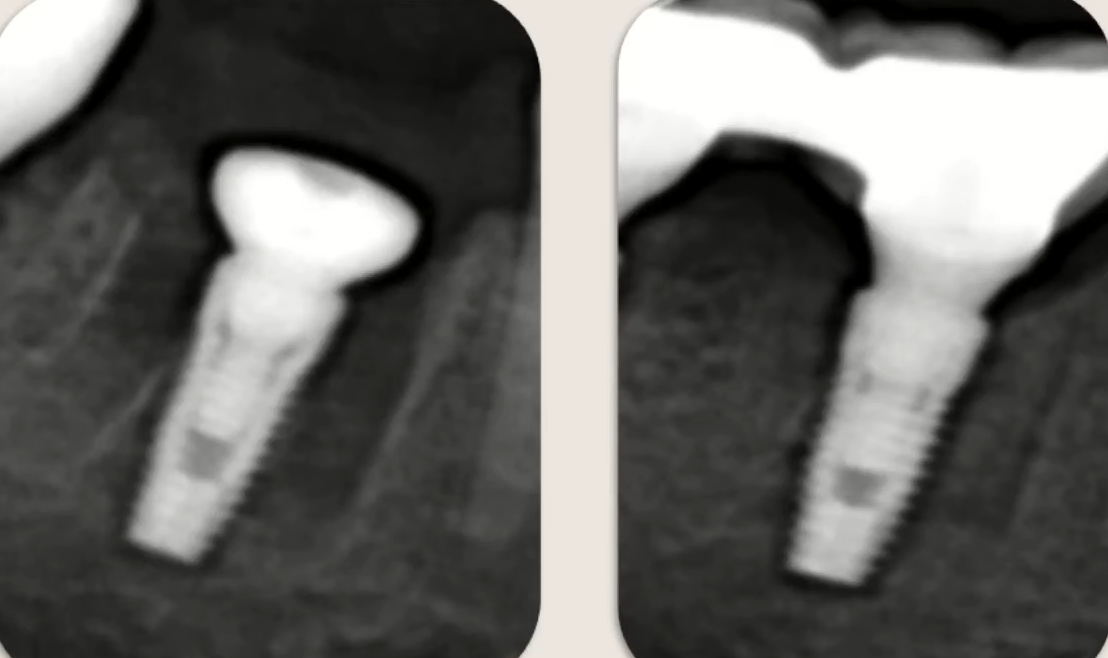

Another example in the image below shows significant bone loss due to incorrect implant design. This is a mandible, and at the time of implant placement, the cortex was distinct and fairly thick. Implants with a microthreaded neck designed for cortical bone anchorage should have been used—perhaps the previously discussed reverse-taper implants. In that case, the cortical bone would not have been damaged and would have been preserved in sufficient volume.

Bone loss in the lower jaw is also due to pressure from the implant neck on the cortical layer and its inevitable resorption. YouTube / Dr. Kamil Khabiev / Dental Guru Academy